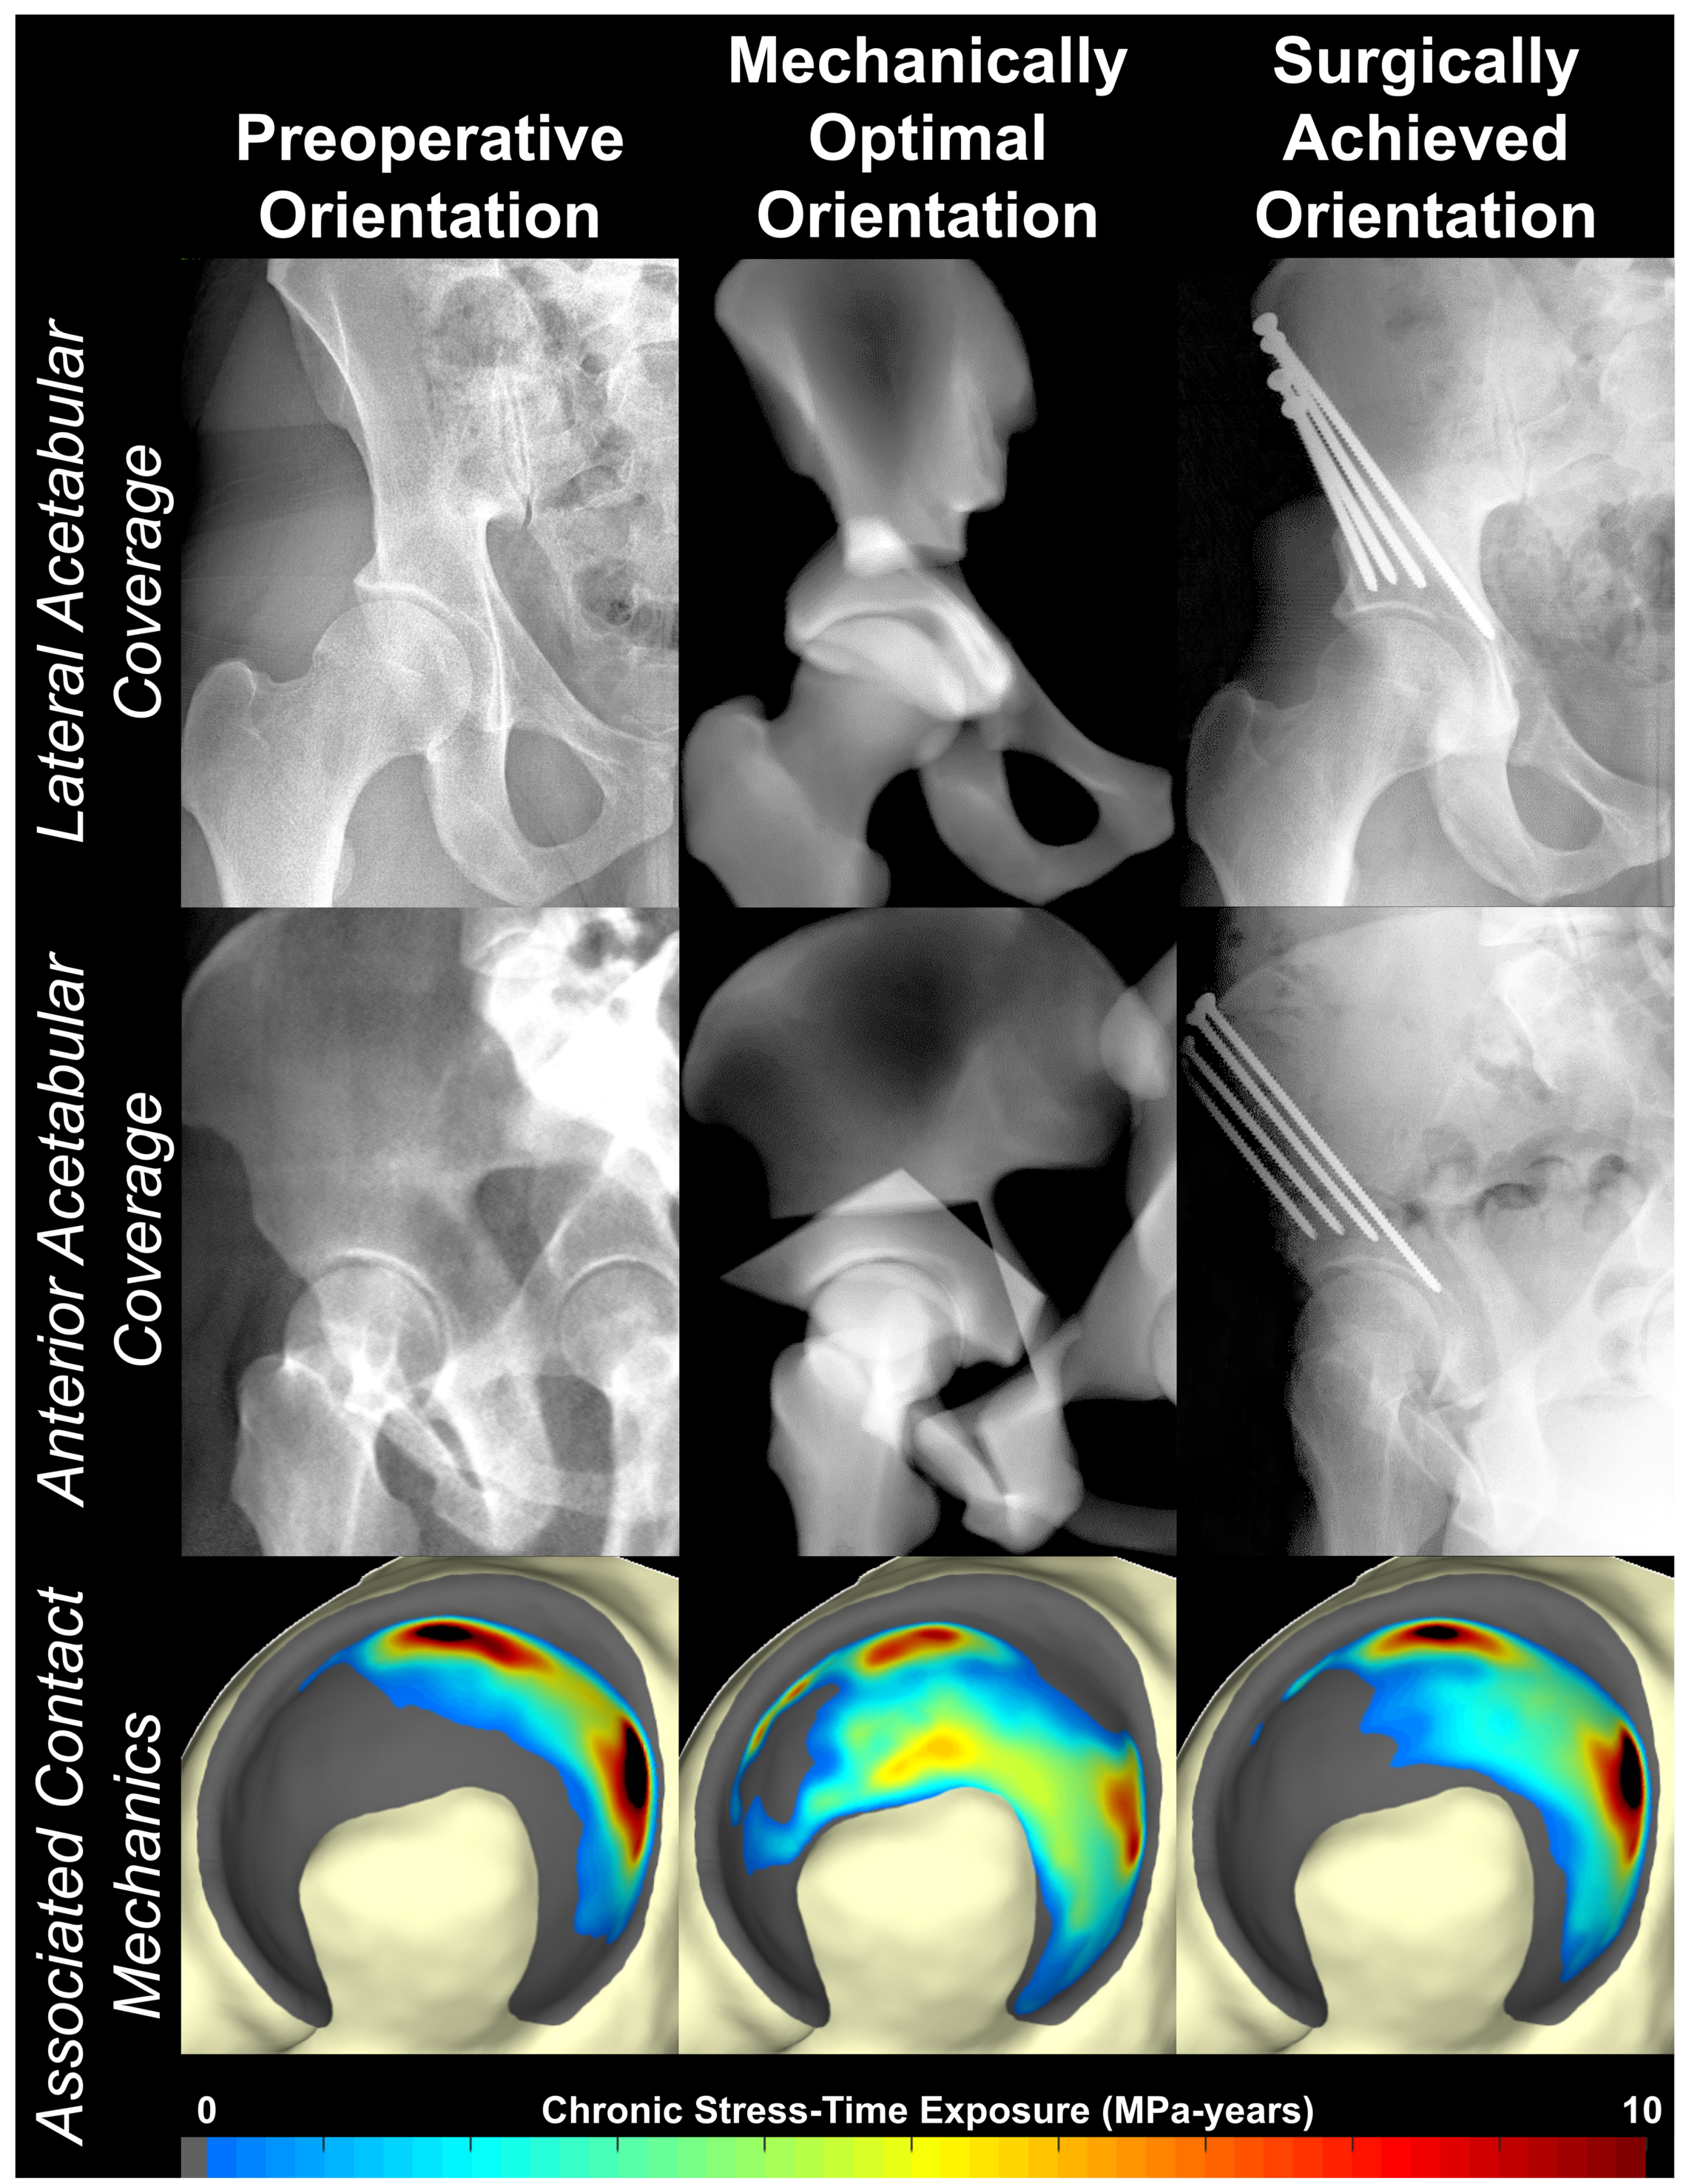

The goal of this project was to use discrete element analysis (DEA), a computational stress analysis technique, to understand how reorienting the acetabular fragment during periacetabular osteotomy (PAO) affects the contact mechanics of the dysplastic hip joint and how those mechanical changes influence patient outcomes.

A 3x3 grid of rainbow contour plots of contact stress distributed across surface renderings of an acetabulum